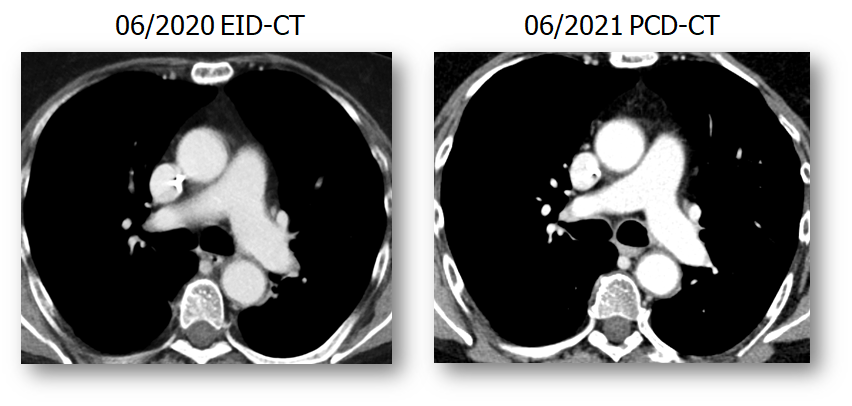

This is particularly noticeable when iodine-containing contrast agents are used, since iodine produces an attenuation of quanta due to the high X-ray density of the contrasted vessels, especially in CT angiography. The absorption of iodine is relatively high, with a “K-edge” (K-shell binding energy for X-ray absorption) of 33.2 keV, so this advantage of photon-counting detectors is particularly prominent and results in higher iodine contrast and a higher contrast-to-noise ratio.

- Virtual coronary calcium scoring based on coronary CTA data sets.

- Improved conspicuity of liver metastases using low-keV virtual monoenergetic imaging series.

- Improved image quality of run-off CTA using low-keV VMI